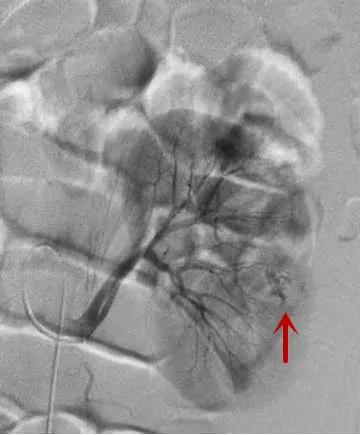

△造影找到出血动脉/找到出血责任动脉/精准栓塞后出血动脉已闭塞